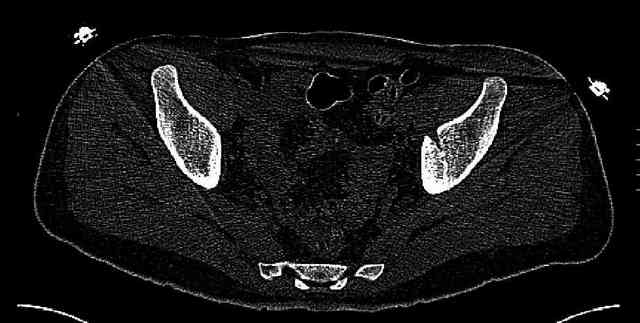

Мужчина 33 лет получил травму в шахте (придавило вагонеткой) 6 недель назад. Изолированное повреждение вертлужной впадины.

В местной больнице отлежал несколько недель на вытяжении. После выписки амбулатрный травматолог направил в институт. На сегодня, похоже, уже имеется неправиильное сращение. См. картинки.

Dear all,A male 23 y.o. injured 6 weeks ago - mine trauma, impacted by a carriage. Isolated injury of the acetabulum. At the initial hosptial was on bed traction some weeks. After discharge visited anotheк orthopaedic surgeon who referred him to our unit. To date looks like a malunion. Images attached. The question is about what to do now - either leave it as is or perform open reduction? If the latter what approach, reduction manoeuvres and fixation would you advice? Thx in advance!

What is your indication for surgical management? What kind of fracture do you think it is? It looks like a transverse type although it has been a couple of years since I looked at an acetabular fracture.

My concern would be that the risk of leaving it malreduced is very high. It appears to be primarily a gap rather than a step in the articular surface. Do you have any CT views that show an articular step?

The last two images from the 3-D CT scan certainly makes the fracture look worse than the plan radiographs.